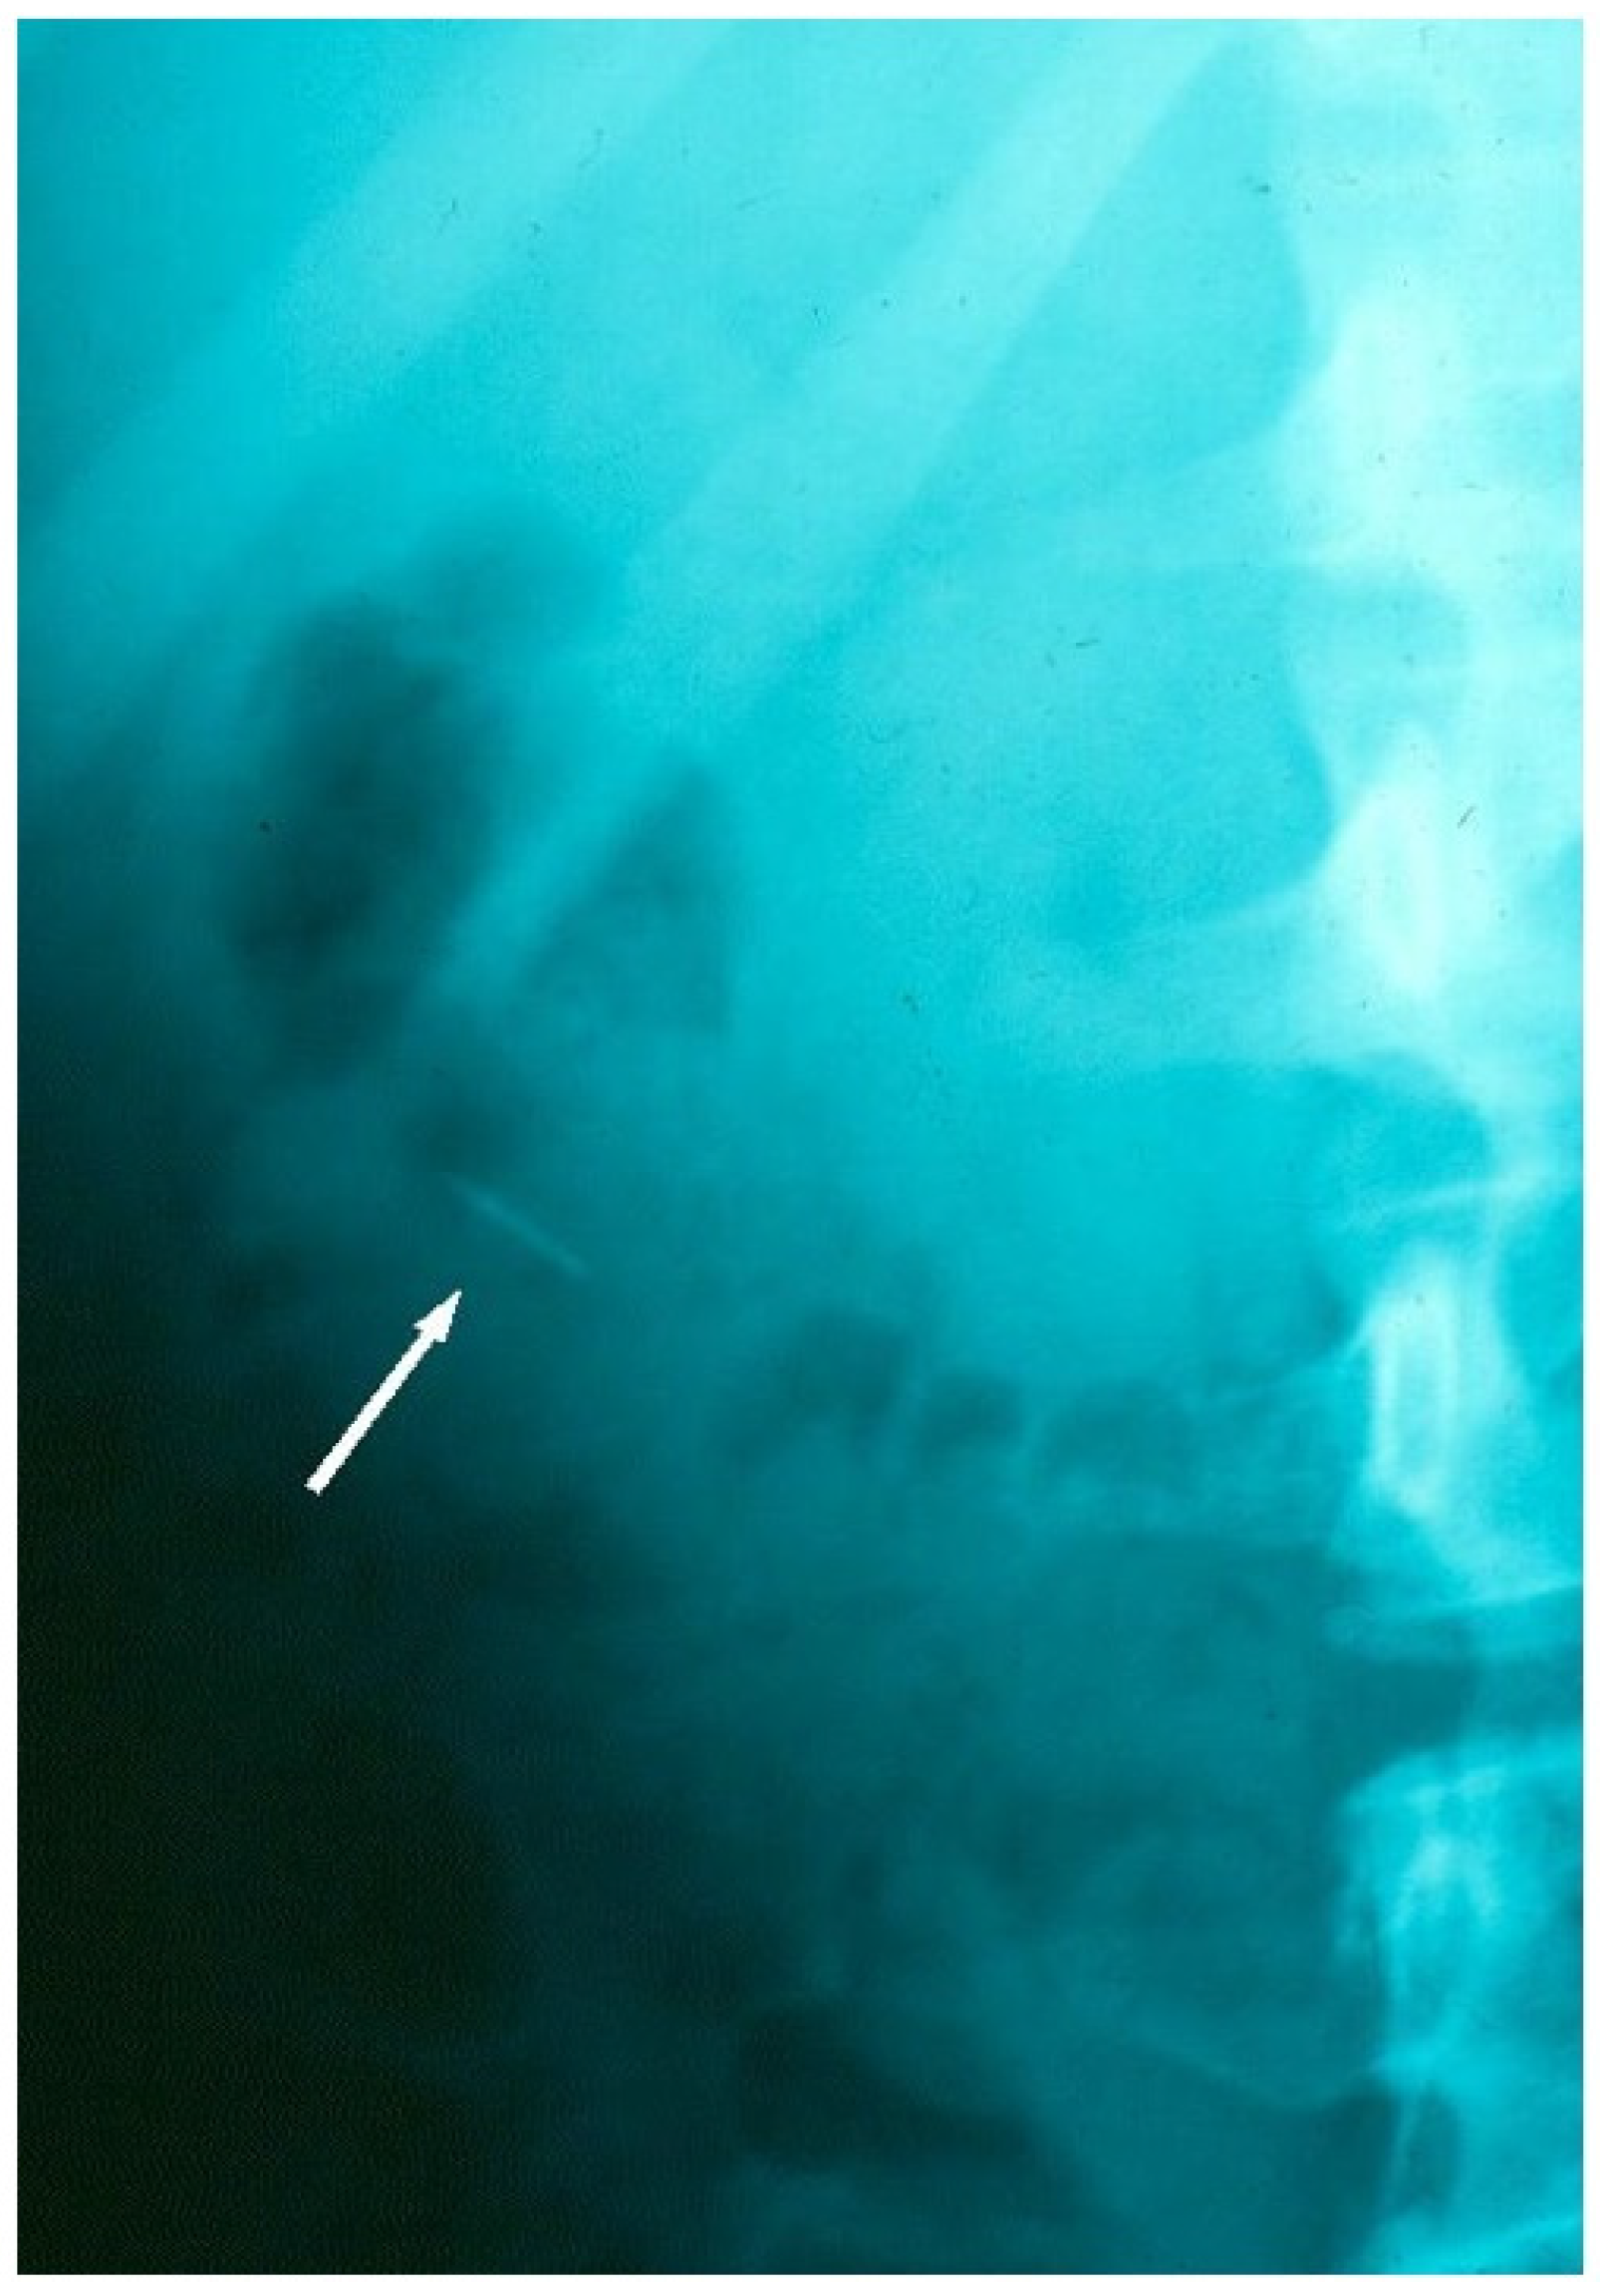

Radiographic tracking view, confirming the archwire fragment location in the colon, during its safe passage through the GIT.